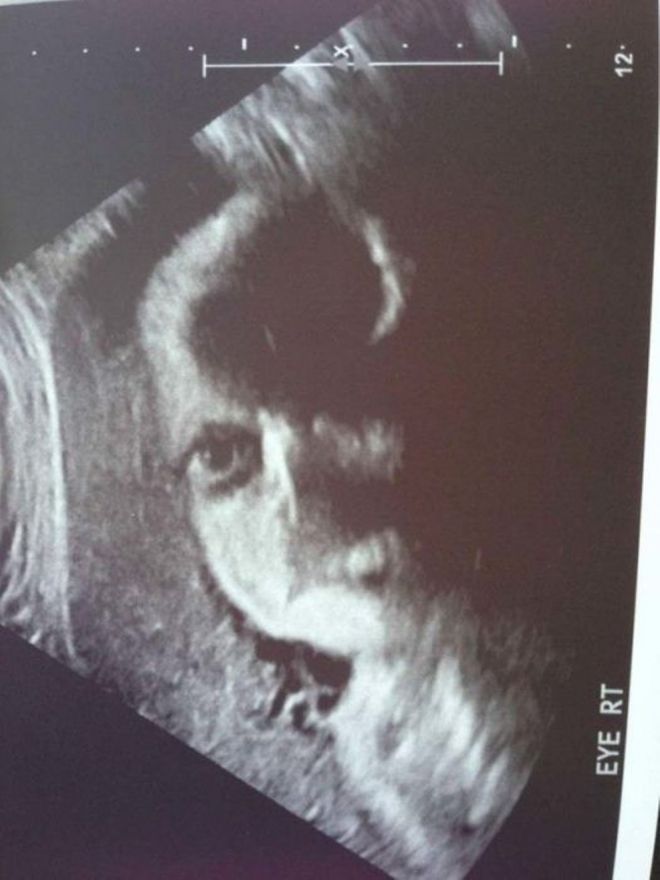

Կարծես թե այս փոքրիկն ինչ-որ բա՞ն է փորձում ասել։